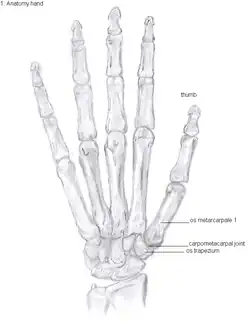

Anatomy

The TMC joint is a synovial joint between the trapezium bone of the wrist and the metacarpal bone at the base of the thumb. This joint is a so-called saddle joint (articulatio sellaris), unlike the CMC joints of the other four fingers which are ellipsoid joints.[17] This means that the surfaces of the TMC joint are both concave and convex.

This shape provides the TMC joint a wide range of motion. Movements include:[18]

The TMC joint is stabilized by 16 ligaments.[19] Of these ligaments, the deep anterior oblique ligament, also known as the palmar beak ligament, is considered to be the most important stabilizing ligament.[20]

Showing the bones of the hand